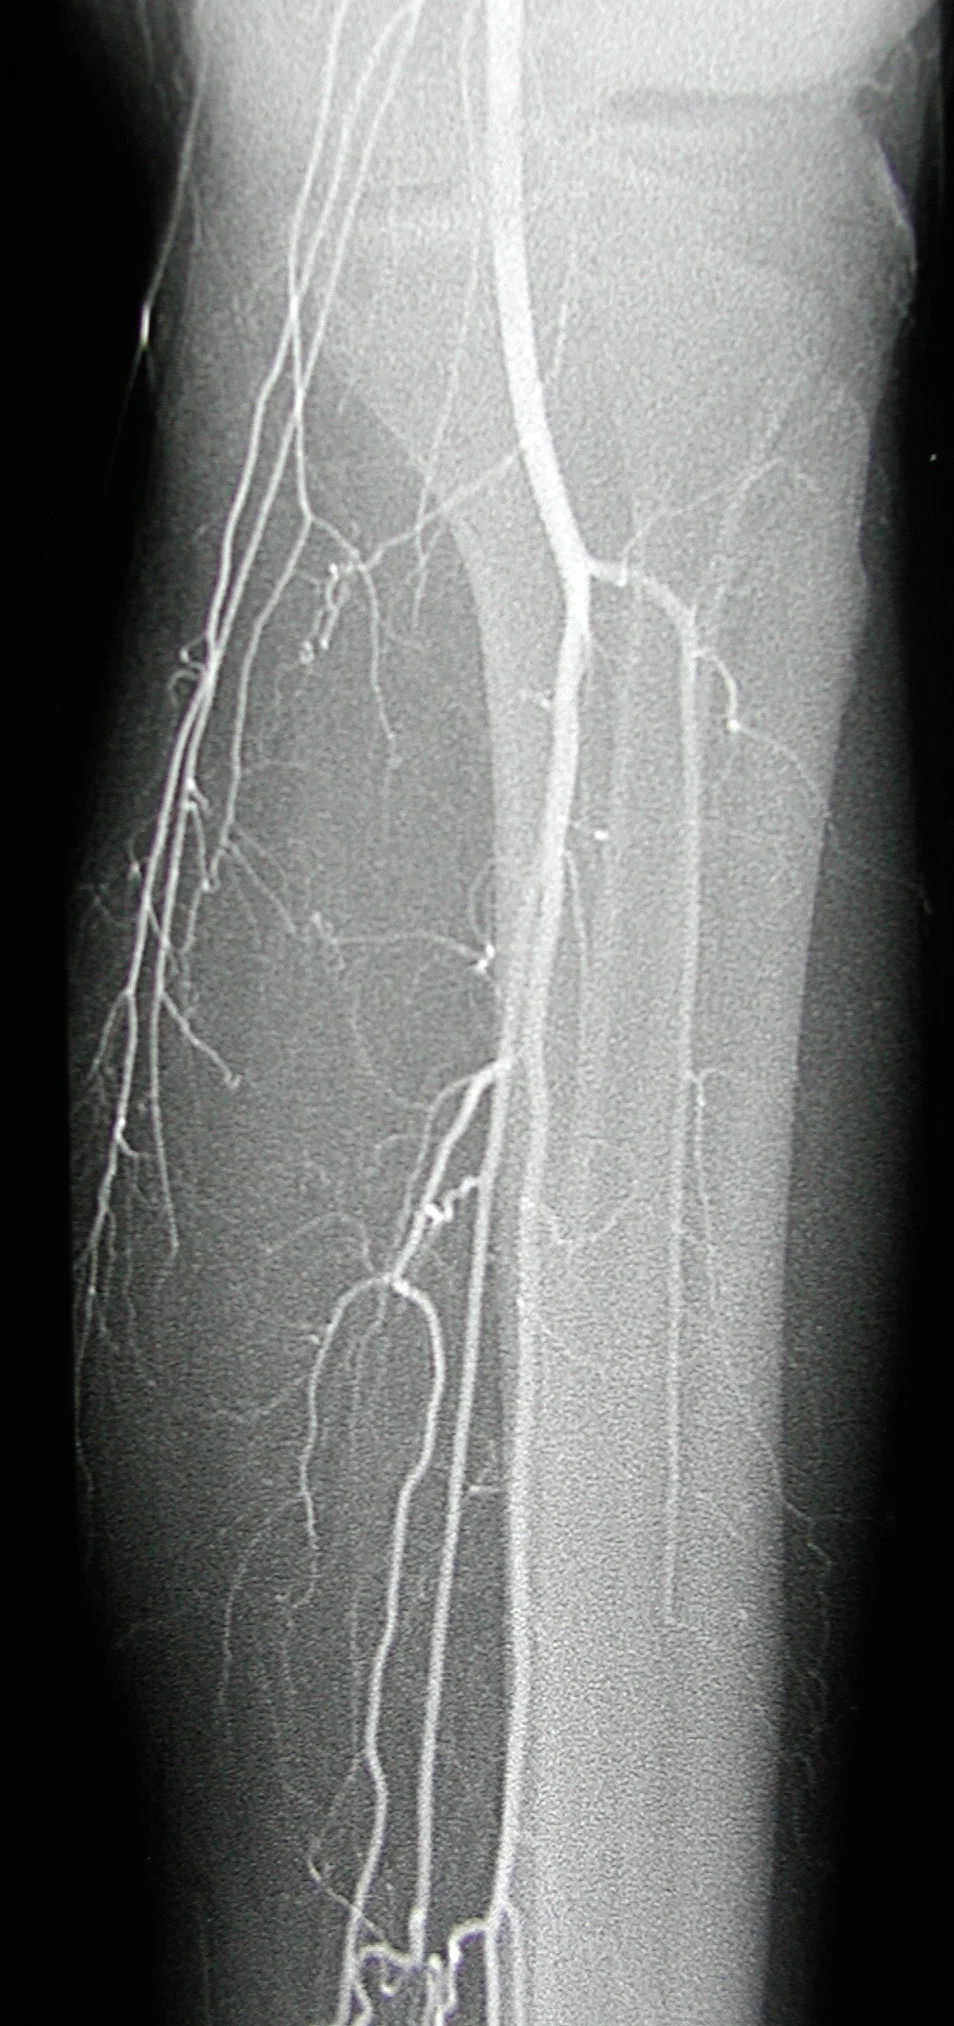

38 year old male with a history of smoking and no history of diabetes, hypertension, or hyperlipidemia who presents with cold and painful feet.